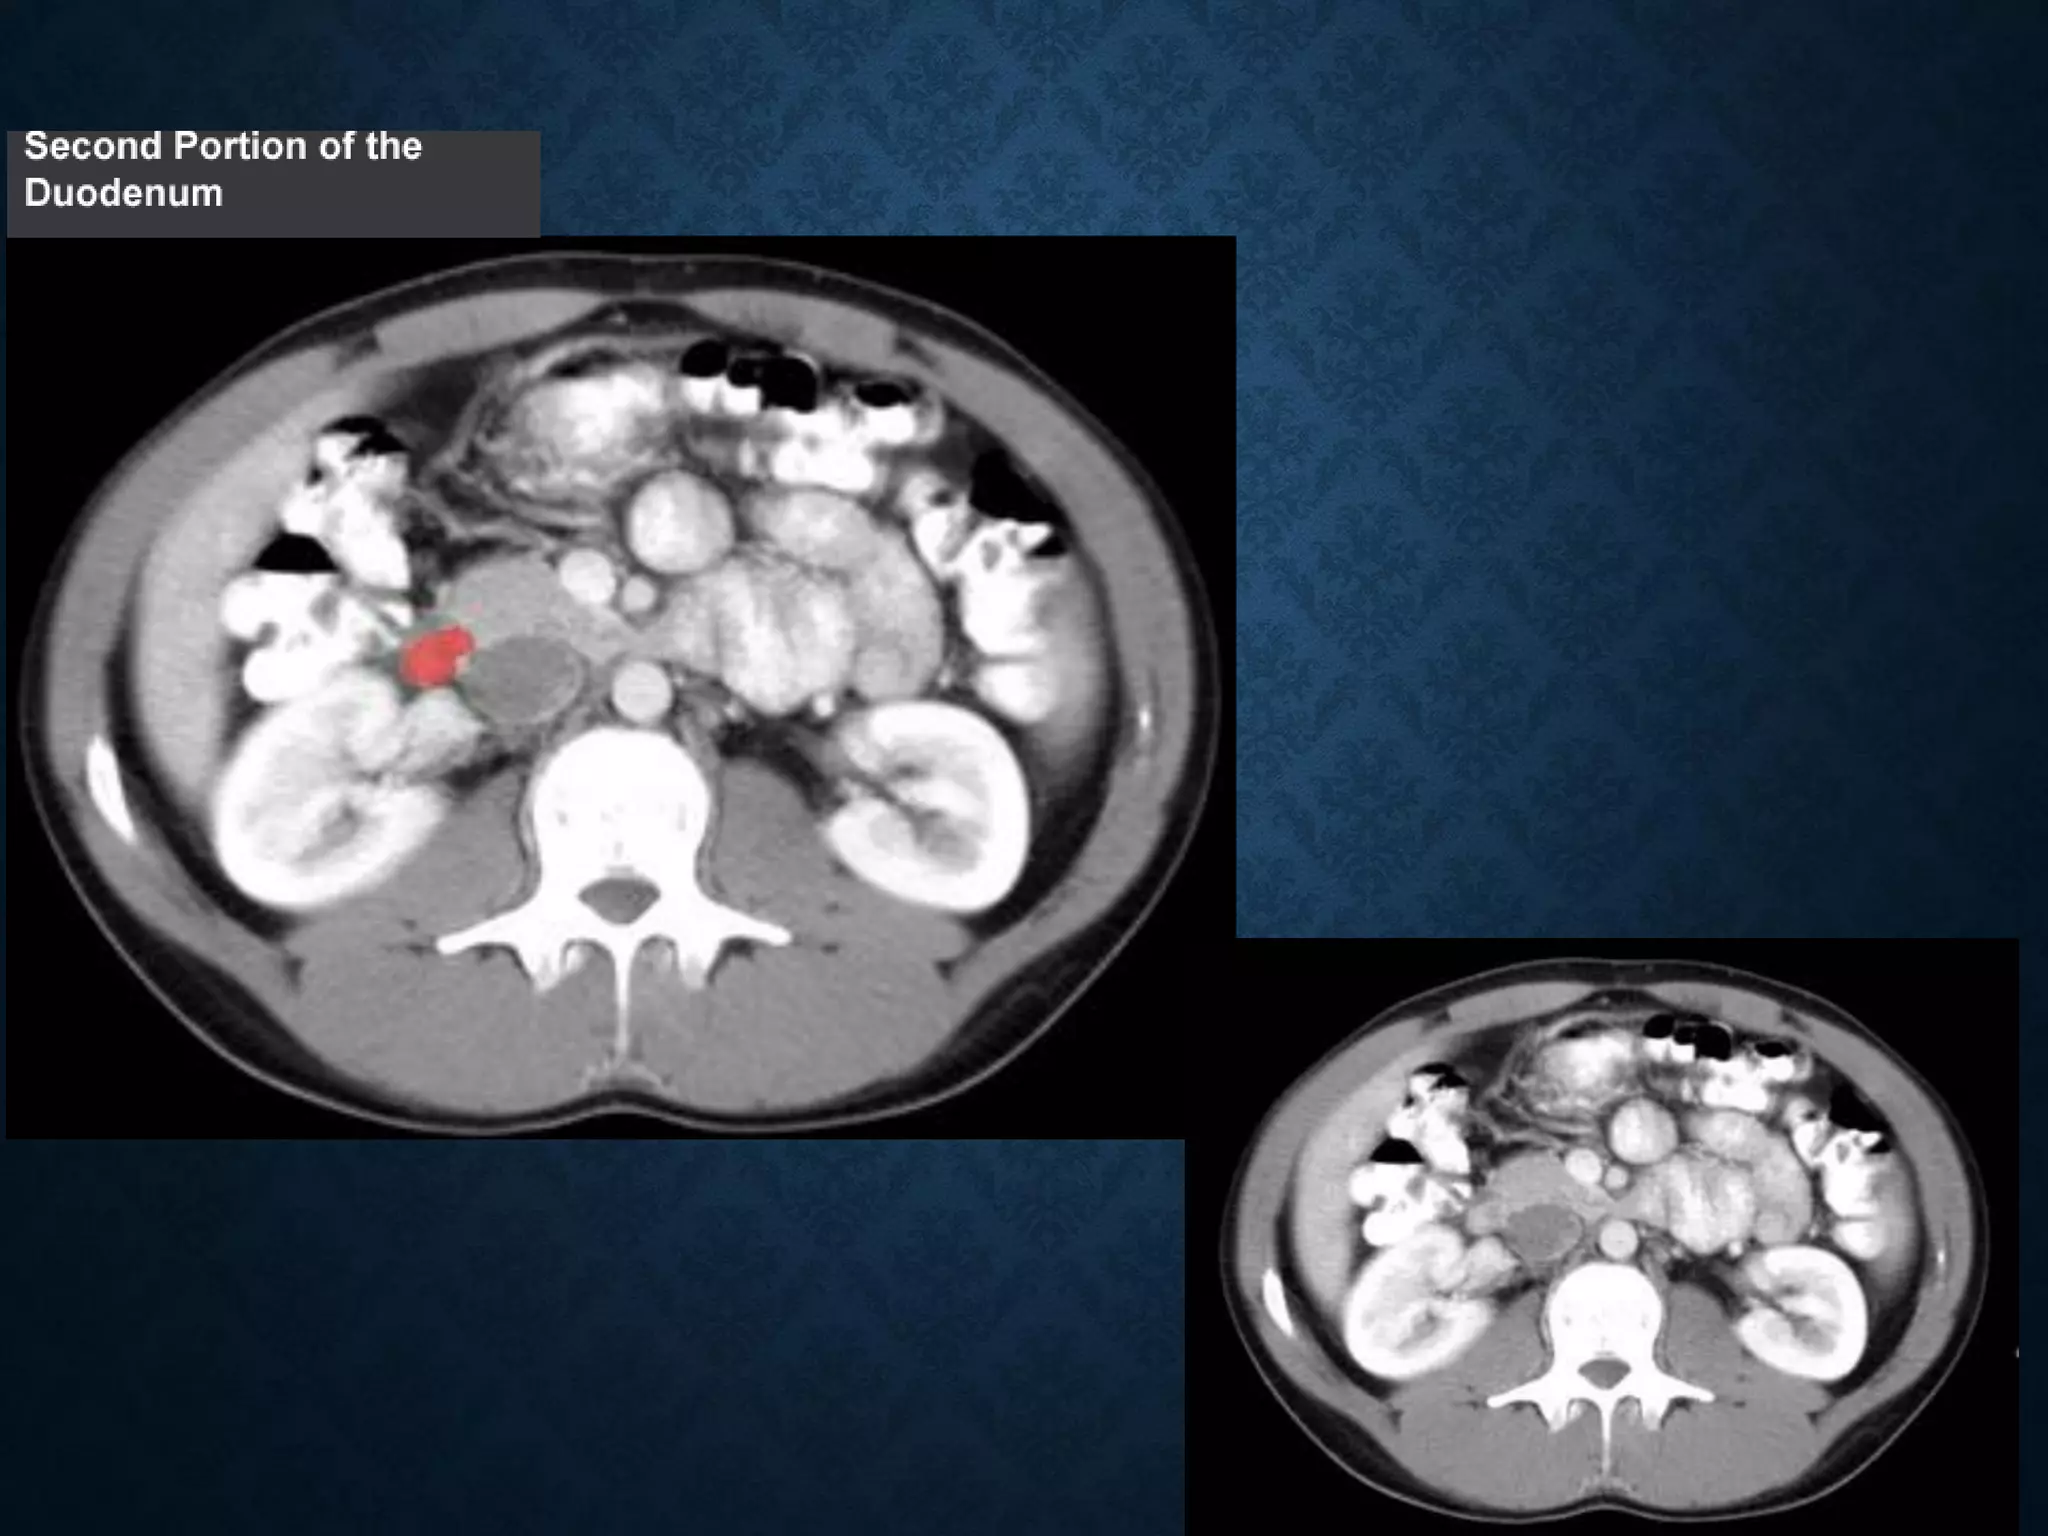

Identify the following structures in the body CT to the right. To view the location of the structure in the image click on

the label at the left and the structure will be indicated in the image. Abdominal CT scans typically begin just above

the diaphragm, so the first slice you see is of the lower chest.

NORMAL ANATOMY- SECTION 9